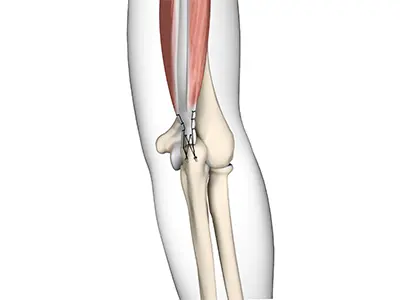

Distal Biceps Repair

The biceps is a large muscle located in the front of your upper arm and runs from the shoulder to the elbow joint.